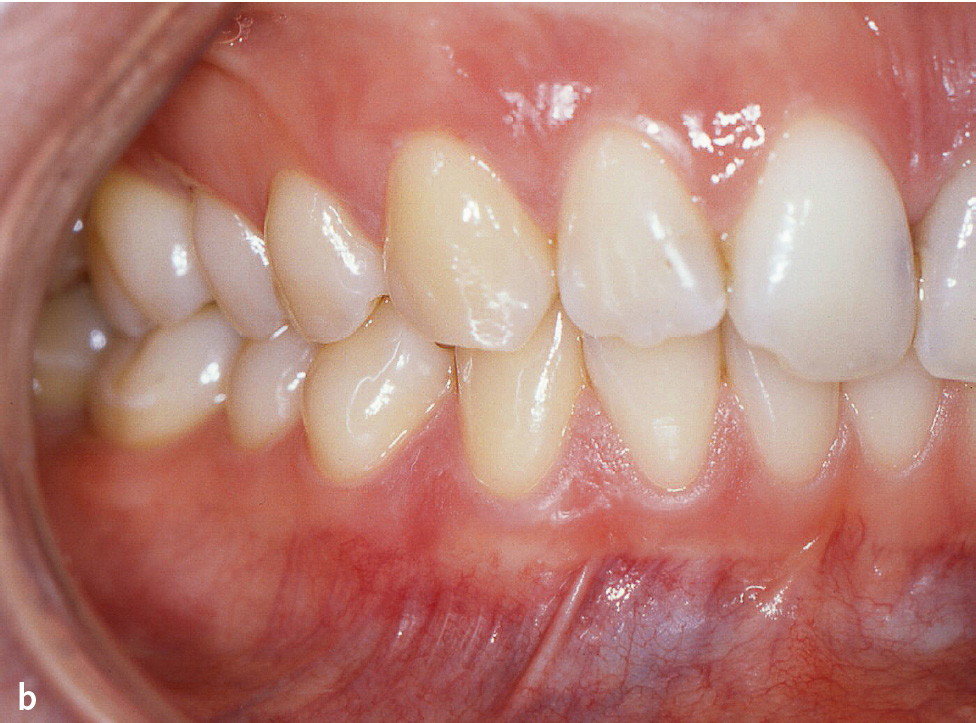

Abb. 4a bis c Patientin im Alter von 24 Jahren mit generalisierter aggressiver Parodontitis18, Parodontitisstadium III (Molaren-Inzisiven-Muster) Grad C. a) Röntgenstatus: Knochenabbau bis ins apikale Wurzeldrittel an den Zähnen 16, 21 und 26 (Stadium III), im Unterkiefer geringerer Knochenabbau bis 50 % der Wurzellänge an Zahn 44, kein Zahnverlust, aber Sondierungstiefen ≥ 6 mm an Zahn 16, Grad-III-Furkationsbeteiligung an Zahn 16 und 26, distal Zahn 16 Knochenabbau 70 % der Wurzellänge (geteilt durch das Lebensalter = 2,9; Grad C). b und c) Klinische Ansicht: keine supragingivale Plaque, Destruktion überschreitet Erwartungen durch Biofilmauflagerungen (Grad C).

In der ICD-10 kommt Parodontitis noch als Chronische Parodontitis (K05.3) vor. Dazu werden gruppiert: Chronische Perikoronitis, Parodontitis complex, -simplex und -o. n. A. (ohne nähere Angaben). Ferner wird die Diagnose Parodontose (K05.4) aufgelistet. Ausdrücklich wird die „juvenile Parodontose“ eingeschlossen3. Als juvenile Parodontitis wurde ein Großteil der klinischen Bilder vor 1999 bezeichnet, die danach aggressive Parodontitis genannt wurden7. Parodontitis, die bereits bei Kindern und Jugendlichen auftritt, bei der die Zerstörung im Vergleich zum Lebensalter sehr fortgeschritten ist oder mehr Zerstörung festzustellen ist, als der vorhandene Biofilm erklären kann (Abb. 4), werden in der neuen Klassifikation mit einem Grad C gekennzeichnet (hohe Progressionsrate)9,10. Wie kann es sein, dass die ICD-10 für die infektiös-entzündliche Zerstörung des Parodonts eine Wortendung verwendet, die allgemein für degenerative Prozesse verwendet wird (-ose)? In vielen Fällen der Parodontitis mit hoher Progressionsrate besteht ein Missverhältnis zwischen der Menge der bakteriellen Ablagerungen sowie der klinisch sichtbaren Entzündung (Schwellung, Rötung) und dem Ausmaß der Gewebedestruktion. Dies führte dazu, dass der Begriff „Periodontosis/Parodontosis“ zum Teil synonym wie juvenile Parodontitis verwendet wurde11. Darüber hinaus gibt es noch Sonstige Krankheiten des Parodonts (K05.5) und Krankheit des Parodonts, nicht näher bezeichnet (K05.6)3.